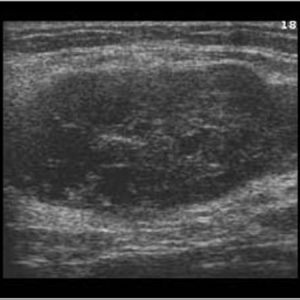

U tuyến nước bọt

Lượt xem: 138» 19-01-2021 -

U tuyến nước bọt

Lượt xem: 153» 19-01-2021 -

U tuyến nước bọt

Lượt xem: 131» 19-01-2021 -

U tuyến nước bọt

Lượt xem: 102» 19-01-2021 -

U tuyến nước bọt

Lượt xem: 146» 19-01-2021 -